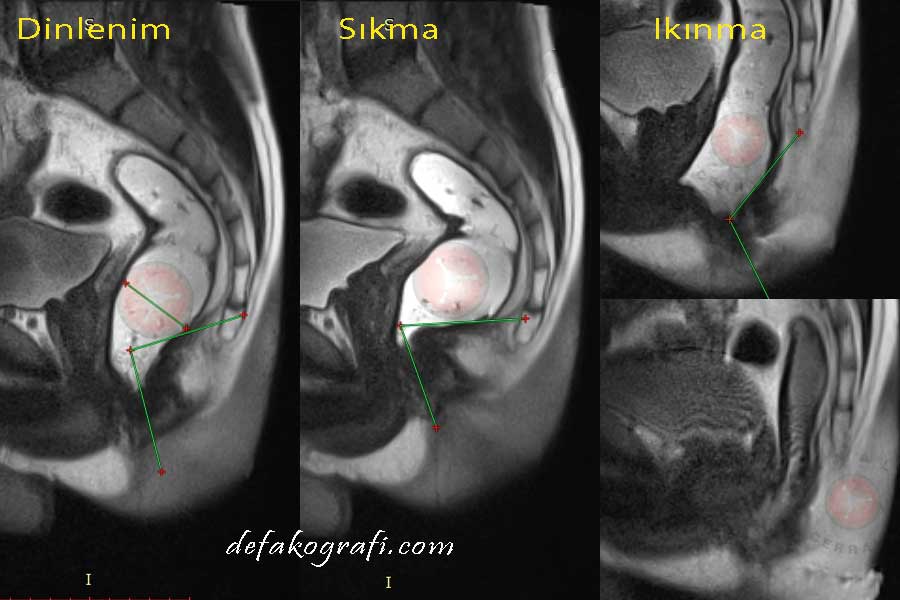

"Defekografi" adı verilen ilaçlı dışkılama filminin ne işe yaradığını anlayabilmek için öncelikle pelvik taban ve anorektal fonksiyonlar hakkında bilgi edinmek gerekir.

Yaşam konfor ve kalitesini etkileyen Anorektal Fonksiyonları; Defekografi adı verilen ilaçlı dışkılama filmiyle hem işlevsel hem yapısal açıdan, Anal Manometri sayesinde işlevsel açıdan, 3D Endoanal Ultrason ile yapısal açıdan inceleyip hasar tespiti yapmak mümkün olur.

Nasıl Yorumlanır? Ne işe Yarar?